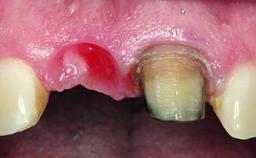

Replacement of an Ankylosed Central Incisor with a Gingival Recession: Tooth Extraction with Socket Grafting and Late Implant Placement with Simultaneous Contour Augmentation

In 2008, a healthy 15-year-old female, non-smoking patient presented at our clinic with a major esthetic problem of tooth 21. Her dental history revealed that the tooth had been avulsed by trauma years before. As a result, the replanted and temporarily splinted tooth had ankylosed and was in severe apical malposition. The ankylosed tooth exhibited a significant gingival recession that disturbed the patient greatly. Due to the patient’s low age and with her skeletal growth not completed, periodic follow-up visits were scheduled to monitor the situation until the patient was old enough for implant therapy.